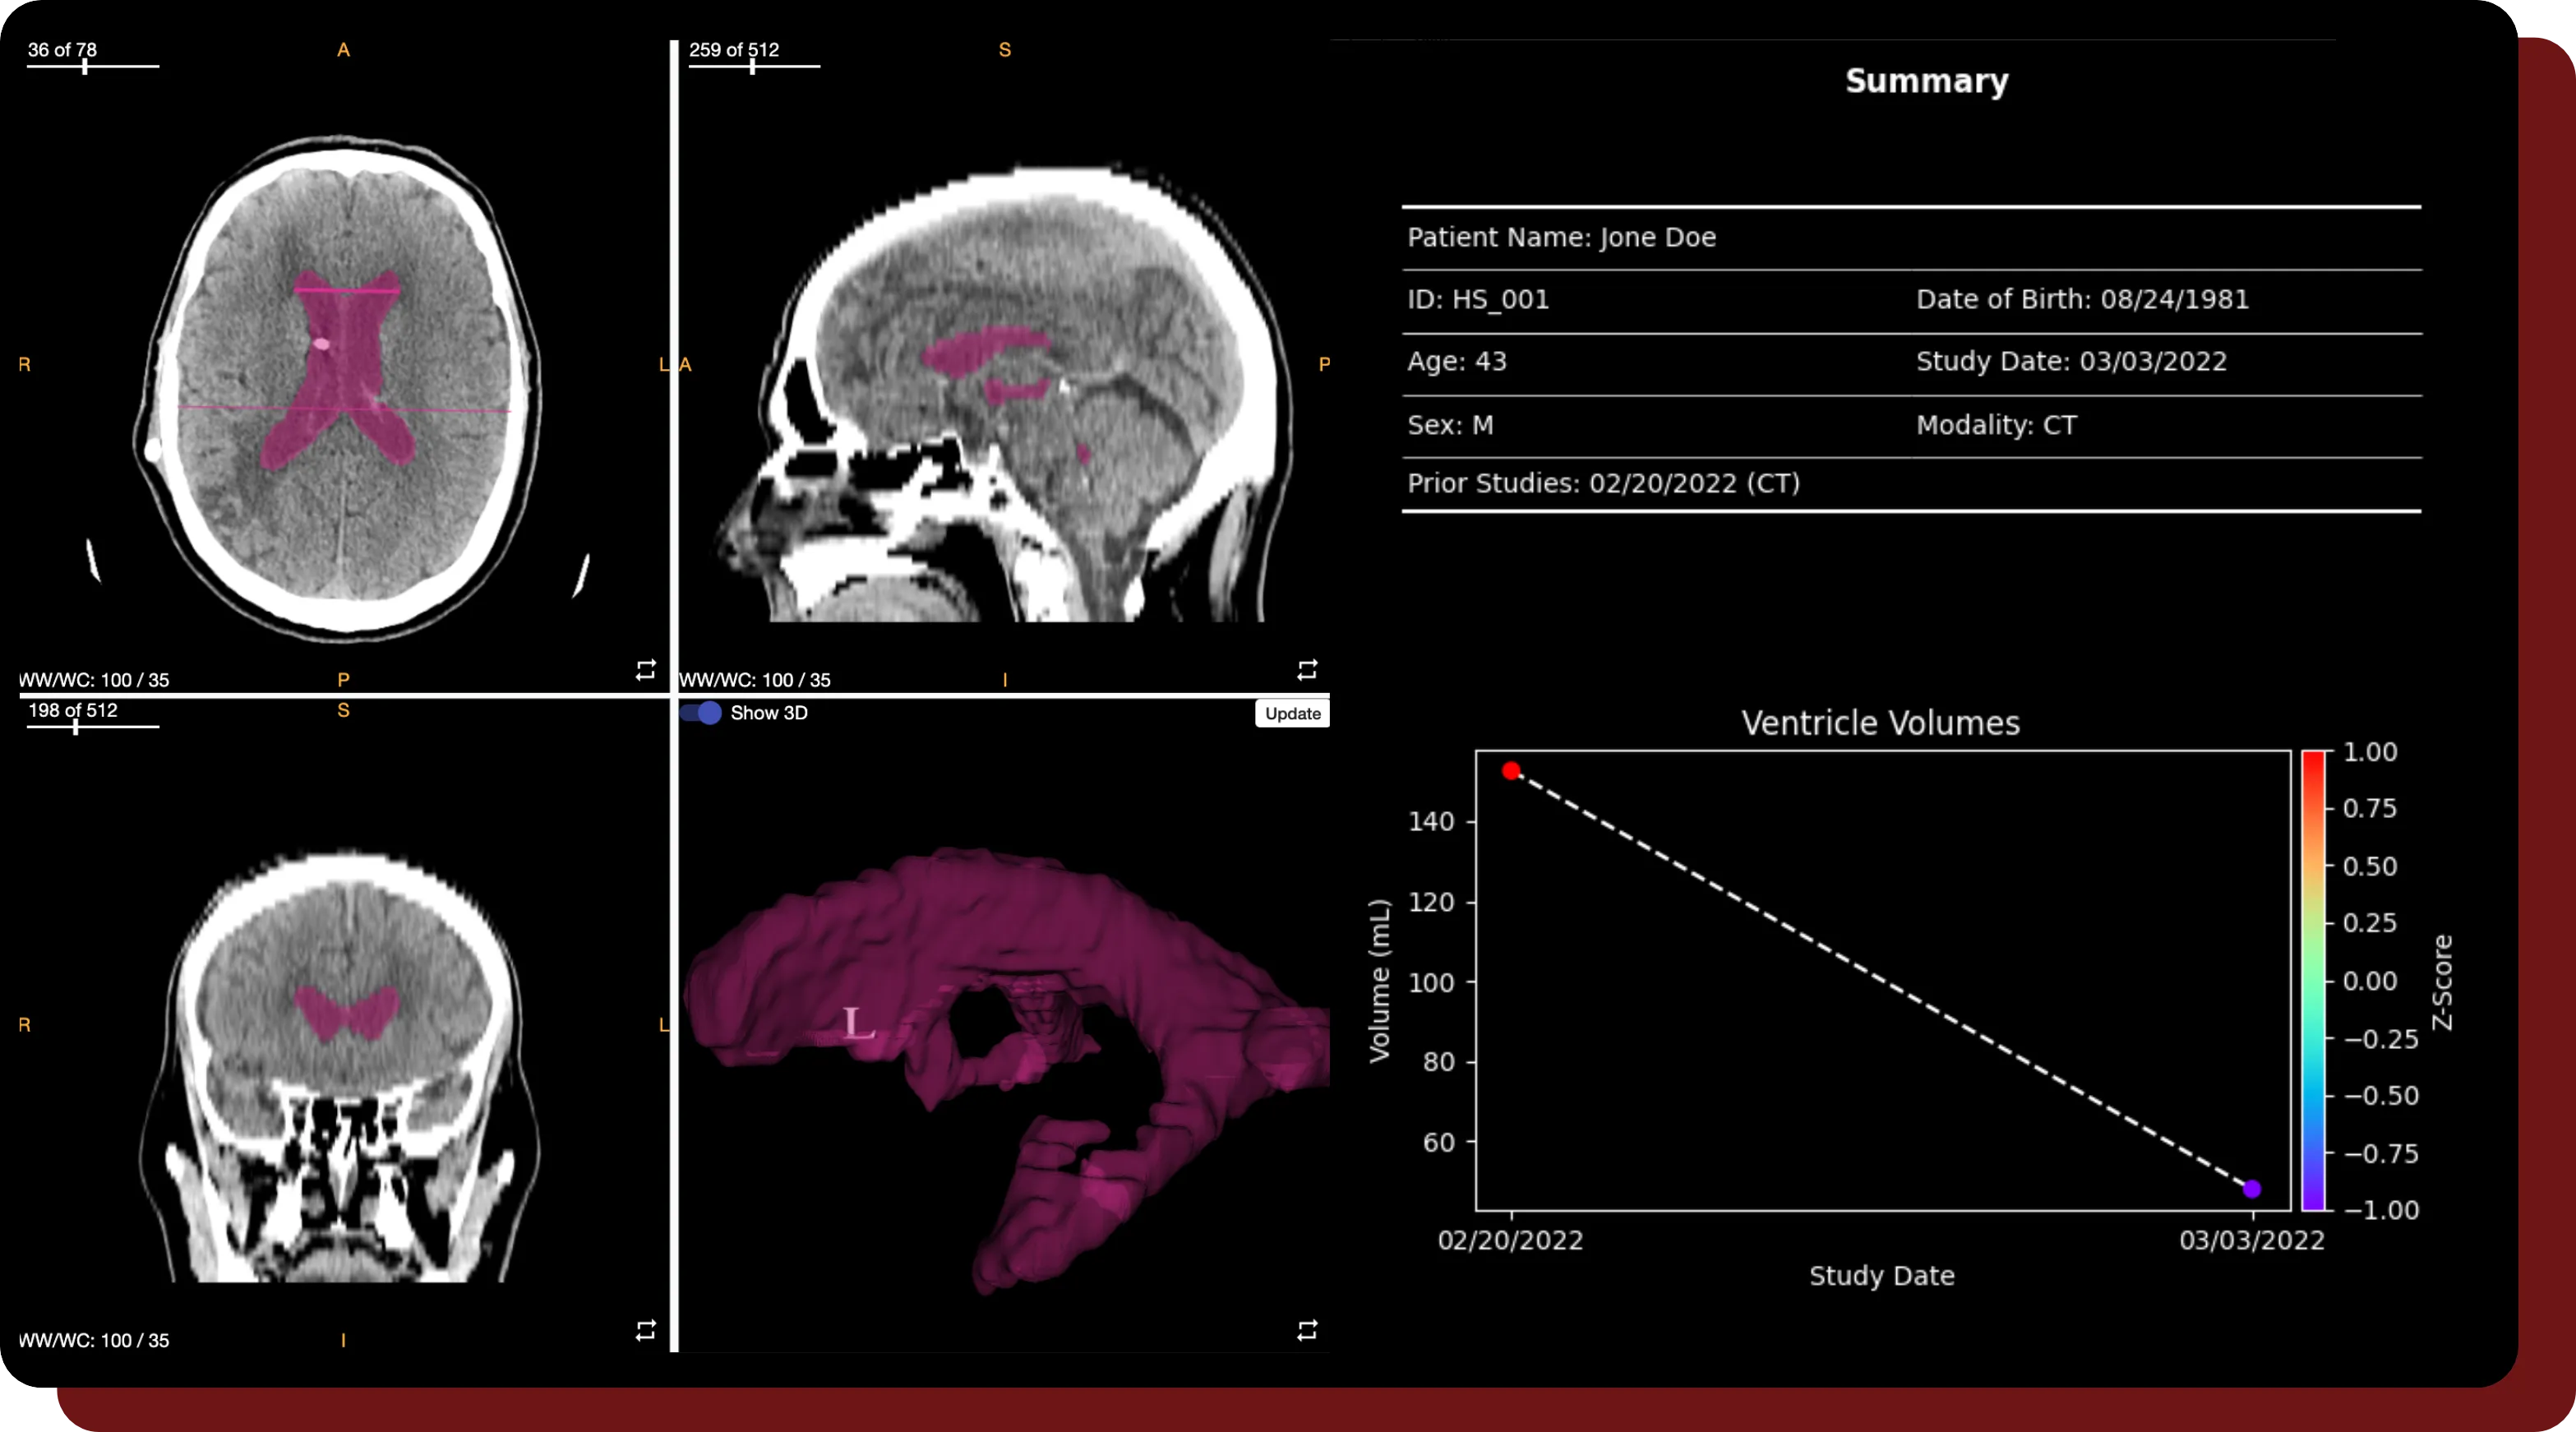

An example of a series with an annotated brain and ventricle within QuantBrain - Ventricle's built-in viewer.

Straightforward Editing & User-Friendly Annotation Tools

• Refine automatic segmentations directly from your browser using QuantBrain - Ventricle's built-in viewer.

• Adjust and fine-tune annotations using a variety of editing tools and viewing windows for optimal analysis.

• QuantBrain - Ventricle's Smart Interpolation tracks annotations on slices and interpolates any changes to unedited slices.

Impactful Quantitative Value Calculations

• QuantBrain - Ventricle reports accurate hydrocephalus and shunt malfunction evaluation through various determining metrics, such as ventricular volume and the Evans Index ratio.

• Results are easily visualized in the form of a generated report.

Longitudinal Tracking

• QuantBrain - Ventricle enables longitudinal analysis across series in order to track changes over time.